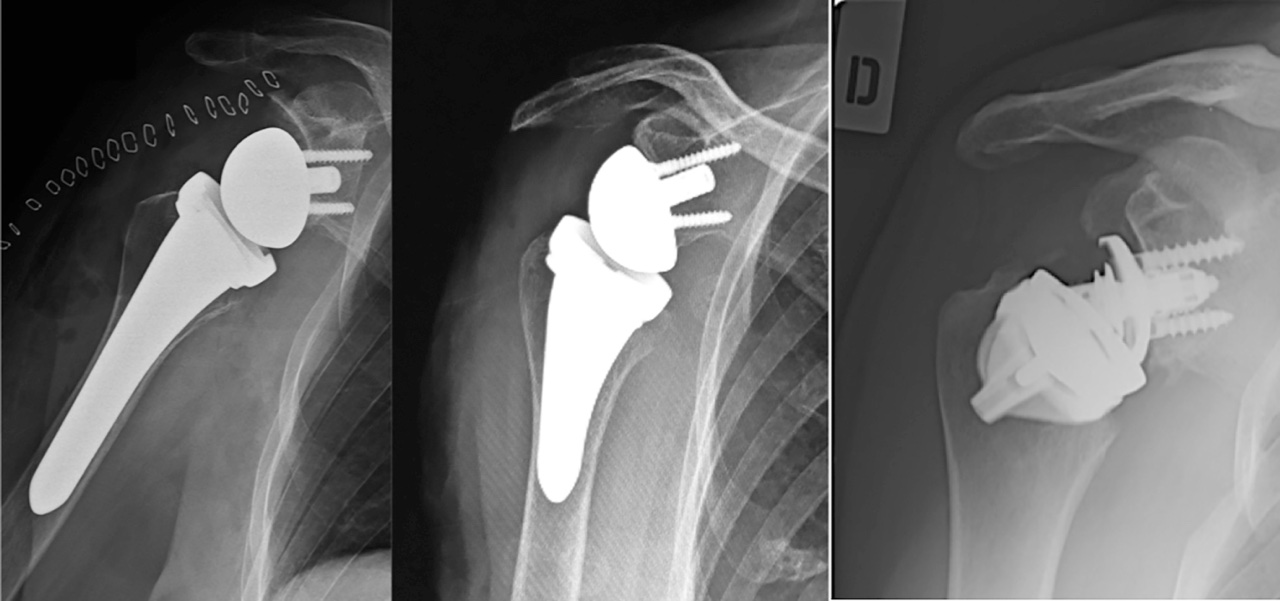

In commercio esistono protesi con stelo convenzionale, con stelo corto o senza stelo (Fig. 1).

L’esigenza di introdurre protesi con stelo corto, o addirittura assente, nasce dal desiderio di preservare osso meta-diafisario che inevitabilmente verrebbe a mancare immediatamente, durante la preparazione metafisaria e del canale midollare, o tardivamente per riassorbimenti legati allo stress shielding. Ovviamente una protesi a stelo corto o senza stelo è indicata in soggetti giovani dove si presuppone ci sia una buona qualità dell’osso metafisario e dove è possibile che in un futuro possa essere necessario un intervento di revisione protesica che, teoreticamente, così dovrebbe essere più semplice7.